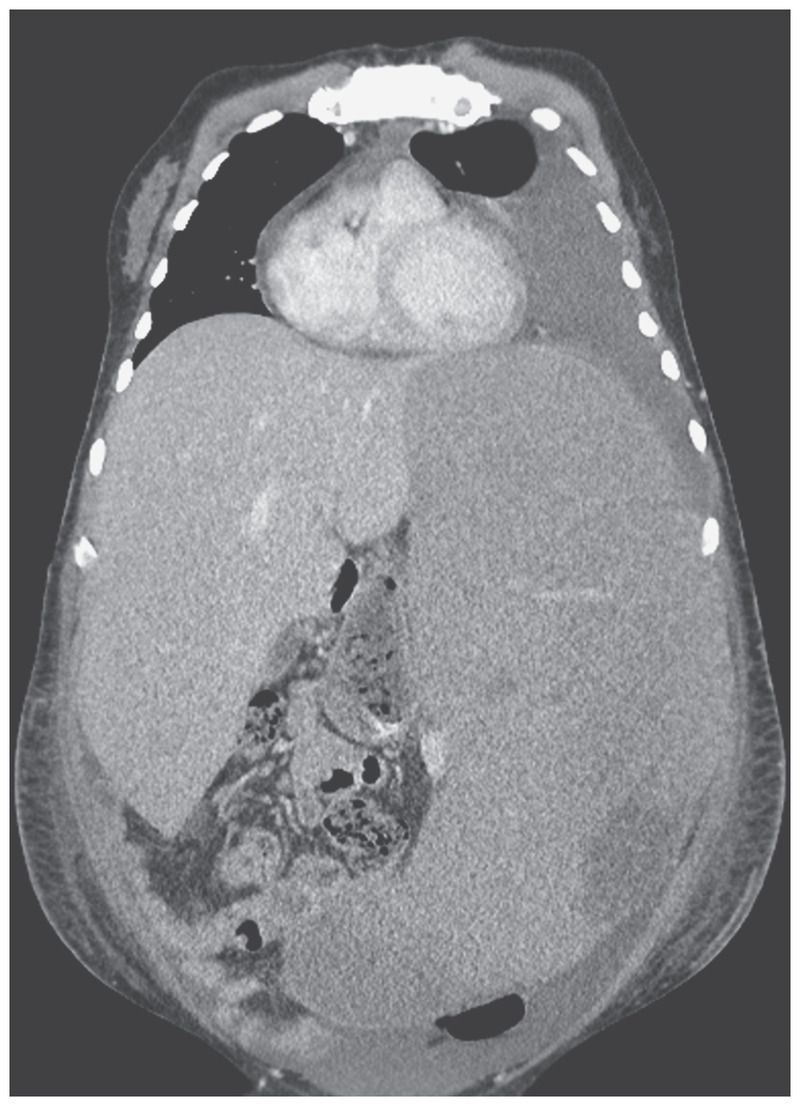

A 35-year-old man presented to the emergency department with a 3-week history of fatigue and painful distention of the left side of his abdomen. He had a history of hepatosplenic T-cell lymphoma and had completed treatment 9 months earlier. Physical examination revealed massive enlargement of the liver and spleen, with the spleen crossing the midline and its lower margin extending into the pelvis. A computed tomographic scan of the abdomen confirmed hepatomegaly and splenomegaly (with the spleen measuring 36 cm in its greatest dimension). The white-cell count was 17,400 per cubic millimeter (reference range, 4000 to 11,000), the hemoglobin level 3.9 g per deciliter (reference range, 13.3 to 17.7), and the platelet count 10,000 per cubic millimeter (reference range, 150,000 to 450,000). A blood smear showed atypical mononuclear cells, intermediate to large in size, with irregular nuclear contours, moderately fine chromatin, prominent nucleoli, and some cytoplasmic blebs. Relapsed hepatosplenic T-cell lymphoma was confirmed on flow cytometry. Other causes of massive splenomegaly include chronic myeloid leukemia, myelofibrosis, hairy-cell leukemia, malaria, Ξ²-thalassemia major, and visceral leishmaniasis. Treatment with immune checkpoint blockade and opioid analgesics was initiated, but the patient died consequent to disease progression 10 weeks after presentation.